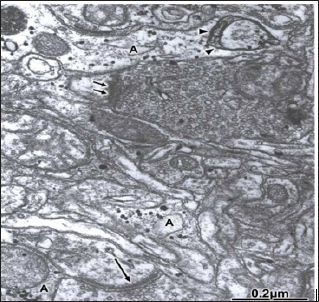

Figure 14: Brain trauma. Right epidural hematoma. Right temporal cortex. Capillary (C) showing the increased activity of endothelial cell luminal membrane, which exhibits the formation of pinocytotic vesicle (short arrow), deep invagination (long arrow), and formation of endothelial vacuoles (V). Note the swollen basement membrane (BM), and the degenerated myelinated axons (AX) in the neighboring neuropil. The arrow indicates the disrupted axo- lemmal membrane, and the circle the granular degeneration of neurofilaments. X 36.000.

In severe and complicated traumatic brain injuries, the endothelial cell luminal membrane of brain capillaries undergoes profound activity changes that characterize the increased cerebrovascular permeability. Such changes are increased formation of micro- and macropinocytotic vesicles and clathrinid- coated vesicles, deep invaginations and formation of incomplete trans endothelia channels, and emission of pseudopods to form endothelial vacuoles [107,115-118].